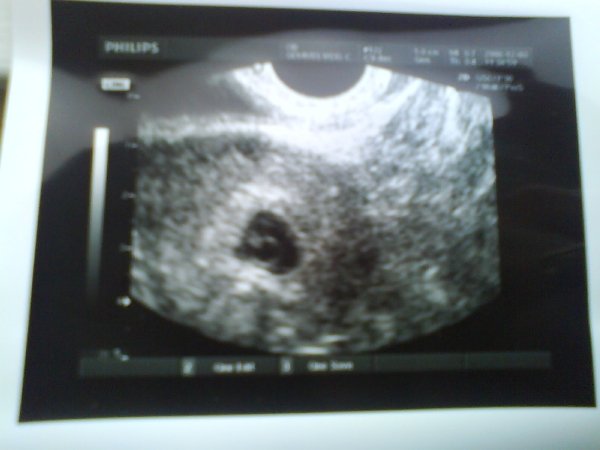

Na, lányok, közben én is előkerültem. Jelentem, van egy 3 mm, jobbról érkezett embrióm. :oops: Felteszem a képet, ami nem a legjobb, mivel a mobilommal készítettem és töltötem fel, illetve a leletet is. Sajnos egy dolgot elfelejtettem, a szívhangot nem néztük meg. Mondjuk ez azért is lett volna fontos, mert ugye elhalt a babám korábban. De annak volt előzménye, ami most meg nincs, és méret szerint (5+6) pont annyi a baba, amennyinek lennie kell, elvégre október 23-án fogant! :lol: :lol:

Kép

Viszont nagyon érdekes összehasonlítani a korábbi felvételekkel, úgyhogy nem is értem miért mondta az UH doki nő, hogy nagy a baba a 3 mm-re... szerintem normális. Az előző alkalommal 6+6 terhességi korban 9 mm volt. Ennyit nő 1 hét alatt??? Nem semmi!!!

Na, mindegy nem filozofálok, jól vagyok, a babóca is rendben, úgyhogy pozitívan nézünk a jövő elébe! :wink: :lol:

Még a pénzekre visszatérve: korábban nem említették, de most 500 Ft-t akartak kérni a képért??!! Aztán azt mondta, hogy odaadja enélkül is. Az agyam eldobom, jó lenne egységessé tenni ezt, ne érezze kellemetlenül magát a kismama. Ki nem sz..ja le az 500 Ft-t egy ilyen alkalommal, de MONDJÁK, IRJÁK KI előtte!!! :twisted: :twisted: :twisted: